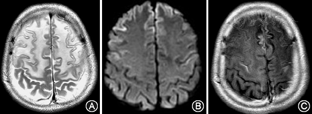

患者男性,16岁,因"阵发性木讷,四肢僵硬、构音障碍10个月"于2016年8月29日入院。患者于10个月前无明显诱因出现阵发性木讷,目光呆滞,持续数十秒后自行好转,而后出现上肢不自主抖动,呈持续性,逐渐出现双上肢先后僵硬,呈屈曲状,不能伸直,后双下肢僵硬,行走不稳。构音障碍,言语不能,饮水呛咳,症状呈进行性加重,自起病来,无发热、头痛,无晕倒、口吐白沫,无肢体偏瘫,无大小便失禁。既往史家族史无特殊。神经系统体检:意识清楚,认知功能尚可,言语不能;K-F环(+);四肢肌张力高,双上肢肌力Ⅳ级,双下肢肌力Ⅴ级,四肢腱反射(+),病理征阴性。生化检查:尿铜792.28 μg /24 h(正常值15~30 μg/24 h);血清铜蓝蛋白测定0.12 g/L (正常值0.2~0.6 g/L);尿常规:隐血3+,蛋白质(±),红细胞832.92个/μl[正常值0~5个/μl];血常规:白细胞计数3.51×109/L[正常值(4~10)×109/L],红细胞计数4.08×1012/L[正常值(4.09~5.74)×1012/L],血红蛋白123 g/L(正常值131~172 g/L),血小板计数78×109/L[正常值(85~303) ×109/L]。凝血四项:纤维蛋白原浓度1.43 g/L(正常值2~4 g/L),凝血酶原时间14.6 s (正常值9~13 s ),国际标准比率1.25 (正常值0.8~1.2),凝血酶原活动度60.1% (正常值70%~150%)。肝功能:碱性磷酸酶210.53 U/L(正常值34~104 U/L),谷氨酰转酞酶58.97 IU/L(正常值5~55 IU/L),纤维结合蛋白127.03 mg/L(正常值180~280 mg/L)。粪便常规+潜血、肾功能、电解质、肌酶谱、C反应蛋白、红细胞沉降率、血脂、餐后2 h血清葡萄糖、叶酸、维生素B12、游离甲状腺素测定等未见异常。患者心电图示窦性心律,大致正常心电图。脑电图:间歇期,左额区见较多中波慢波及尖波,尖慢波;诊断提示:间歇期,痫样放电及慢波,脑区性,左额著。上腹部CT提示肝硬化、脾肿大。颅脑磁共振平扫:双侧额、顶、颞叶脑沟变窄,脑组织肿胀,呈稍长T1稍长T2信号(图1A),DWI呈脑回样高信号(图1B),双侧豆状核、丘脑及外囊、胼胝体、脑干背侧呈片状稍长T1、稍长T2信号,双侧苍白球及小脑齿状核呈等T1、短T2信号(图2)。颅脑增强扫描:双侧额顶叶脑回线样明显强化(图1C)。

本文HLD患者颅脑MRI表现为相对非典型的双侧额、顶、颞叶脑沟变窄,脑组织肿胀,呈稍长T1稍长T2信号,弥散加权成像呈脑回样高信号,增强提示双侧额顶叶脑回线样明显强化以及HLD典型的表现如双侧豆状核、丘脑及外囊、胼胝体、脑干背侧呈片状稍长T1稍长T2信号。脑回线样强化与血脑屏障破坏有关,且脑实质表面强化通常系血管性疾病或炎症性疾病所致[7]。患者有HLD罕见的癫痫发作[8],癫痫所致血管舒张也可导致脑回线样强化。结合国外1例额叶脑回线样强化伴有癫痫发作的HLD患者在抗癫痫治疗1个月后,癫痫症状和脑回线样强化消失,然而额叶皮质下白质影像学改变仍存在且范围相对更大[9],可以推测脑回线样强化与癫痫发作相关,可能是癫痫发作导致脑回线样强化,加剧了脑白质病变。相关研究还发现[8],HLD患者中有癫痫发作者比无发作者有更多的脑白质病变,特别是额叶皮质下病变与癫痫发作呈显著相关。且提示未干预控制的HLD患者癫痫发作,MRI上可能出现脑白质空泡。癫痫发作不是HLD患者常见表现,其往往合并有广泛白质病变[10,11]。目前癫痫与皮质下白质损害因果关系暂不明确。由于HLD影像学存在多样性,诊断应该拓宽思路,还需结合临床病史,及其余辅助检查。